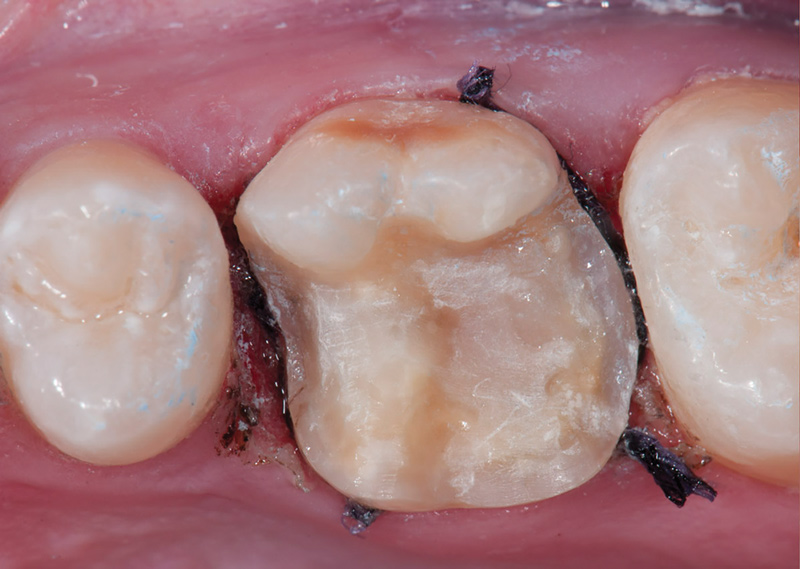

Fig 9. Preoperative view (Fig 9), preparation with composite block-out restoration (Fig 10), and final cementation of CL-IIb material (Fig 11) (final ceramic contour and stain by Steve Lee, CDT, MDC).

Figure 9

Fig 10. Preoperative view (Fig 9), preparation with composite block-out restoration (Fig 10), and final cementation of CL-IIb material (Fig 11) (final ceramic contour and stain by Steve Lee, CDT, MDC).

Figure 10

Fig 11. Preoperative view (Fig 9), preparation with composite block-out restoration (Fig 10), and final cementation of CL-IIb material (Fig 11) (final ceramic contour and stain by Steve Lee, CDT, MDC).

Figure 11